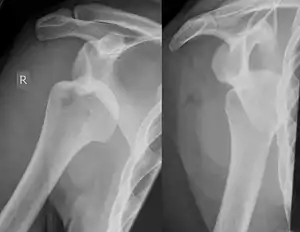

Bankart's fractureArthur BankartFracture of anterior glenoid associated with anterior shoulder dislocationExternal rotation and abduction of shoulder[2][3]

Hill–Sachs fractureHarold Arthur Hill

Maurice David Sachs

impacted posterior humeral head fracture occurring during anterior shoulder dislocationHill Sachs Lesion Archived 2020-09-20 at the Wayback Machine at Wheeless' Textbook of Orthopaedics online